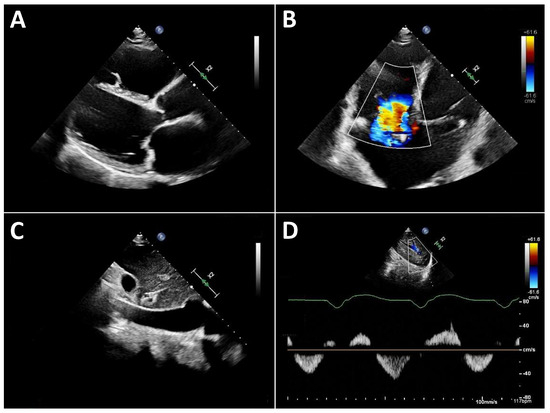

Routine Echocardiographic Assessment in LVAD Patients—A Structured Approach to Acquisition and Interpretation

by Nicolas Merke, Felix Schoenrath, Evgenij Potapov and Jan Knierim

J. Cardiovasc. Dev. Dis. 2026, 13(2), 70; https://doi.org/10.3390/jcdd13020070 - 30 Jan 2026

Durable left ventricular assist devices (LVADs) are an established and highly effective therapy for patients with advanced heart failure. Ongoing technological improvements and structured follow-up programs have significantly enhanced device durability, reduced complications, and improved long-term survival. Consequently, a growing number of patients with LVAD support require long-term outpatient care and increasingly present to both specialized and non-specialized hospitals, including for admissions unrelated to heart failure. In this context, echocardiography plays a central role. It is essential not only for routine follow-up at dedicated LVAD clinics but also for the assessment of cardiac status during inpatient admissions for extracardiac conditions. However, echocardiographic evaluation in LVAD patients is technically demanding and requires a solid understanding of LVAD physiology, device–heart interactions, and the specific hemodynamic conditions of continuous-flow support. Without this knowledge, standard echocardiographic parameters may be misleading. This review provides sonographers and cardiologists with a practical, clinically oriented framework for routine transthoracic echocardiography in patients with durable LVAD support. We summarize key principles of LVAD hemodynamics, discuss interpretation of LVAD console parameters, propose a standardized imaging protocol, and outline a structured approach to common echocardiographic findings in routine ambulatory and inpatient settings. Full article